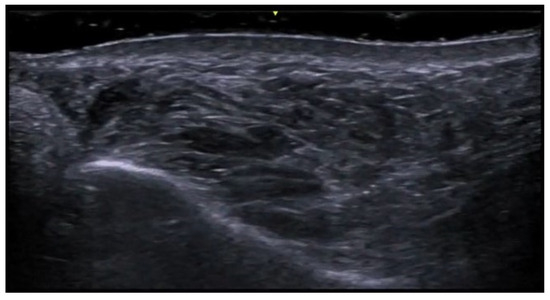

- Granieri, G.; Michelucci, A.; Manzo Margiotta, F.; Cei, B.; Vitali, S.; Romanelli, M.; Dini, V. The Role of Ultra-High-Frequency Ultrasound in Pyoderma Gangrenosum: New Insights in Pathophysiology and Diagnosis. Diagnostics 2023, 13, 2802. [Google Scholar] [CrossRef] [PubMed]